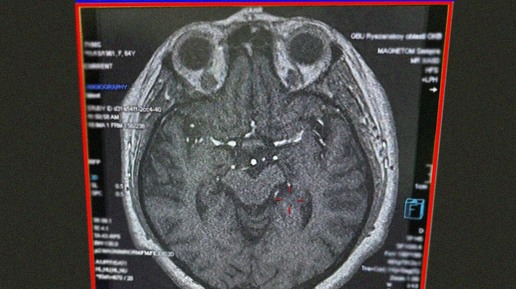

В ОКБ Рязани успешно провели 100-ю операцию по трансплантации почки, что стало юбилейным событием для учреждения. Об этом сообщило министерство здравоохранения региона. С начала 2025 года в больнице было проведено уже 27 подобных операций, что является рекордом за всю историю работы учреждения. Цифра 100 — это не просто статистический показатель. Каждая из этих операций — это спасенная жизнь и восстановленная надежда для пациентов и их близких...

Первая в Рязанской области операция по одновременной пересадке почки и поджелудочной железы пройдет в ОКБ

В ОКБ готовятся к уникальной операции — первой в регионе одновременной пересадке почки и поджелудочной железы. Об этом сообщила ГТРК «Ока». Эта сложная и рискованная операция показана пациентам, страдающим от терминальной стадии почечной недостаточности на фоне сахарного диабета. Подобные операции в России проводятся редко — всего около 30 в год. Чаще всего больных из регионов направляют в Москву для такого вмешательства. При этом возраст не является определяющим фактором. В ОКБ врачи проведут первую в регионе операцию такого типа совместно с коллегами из центра имени Шумакова...